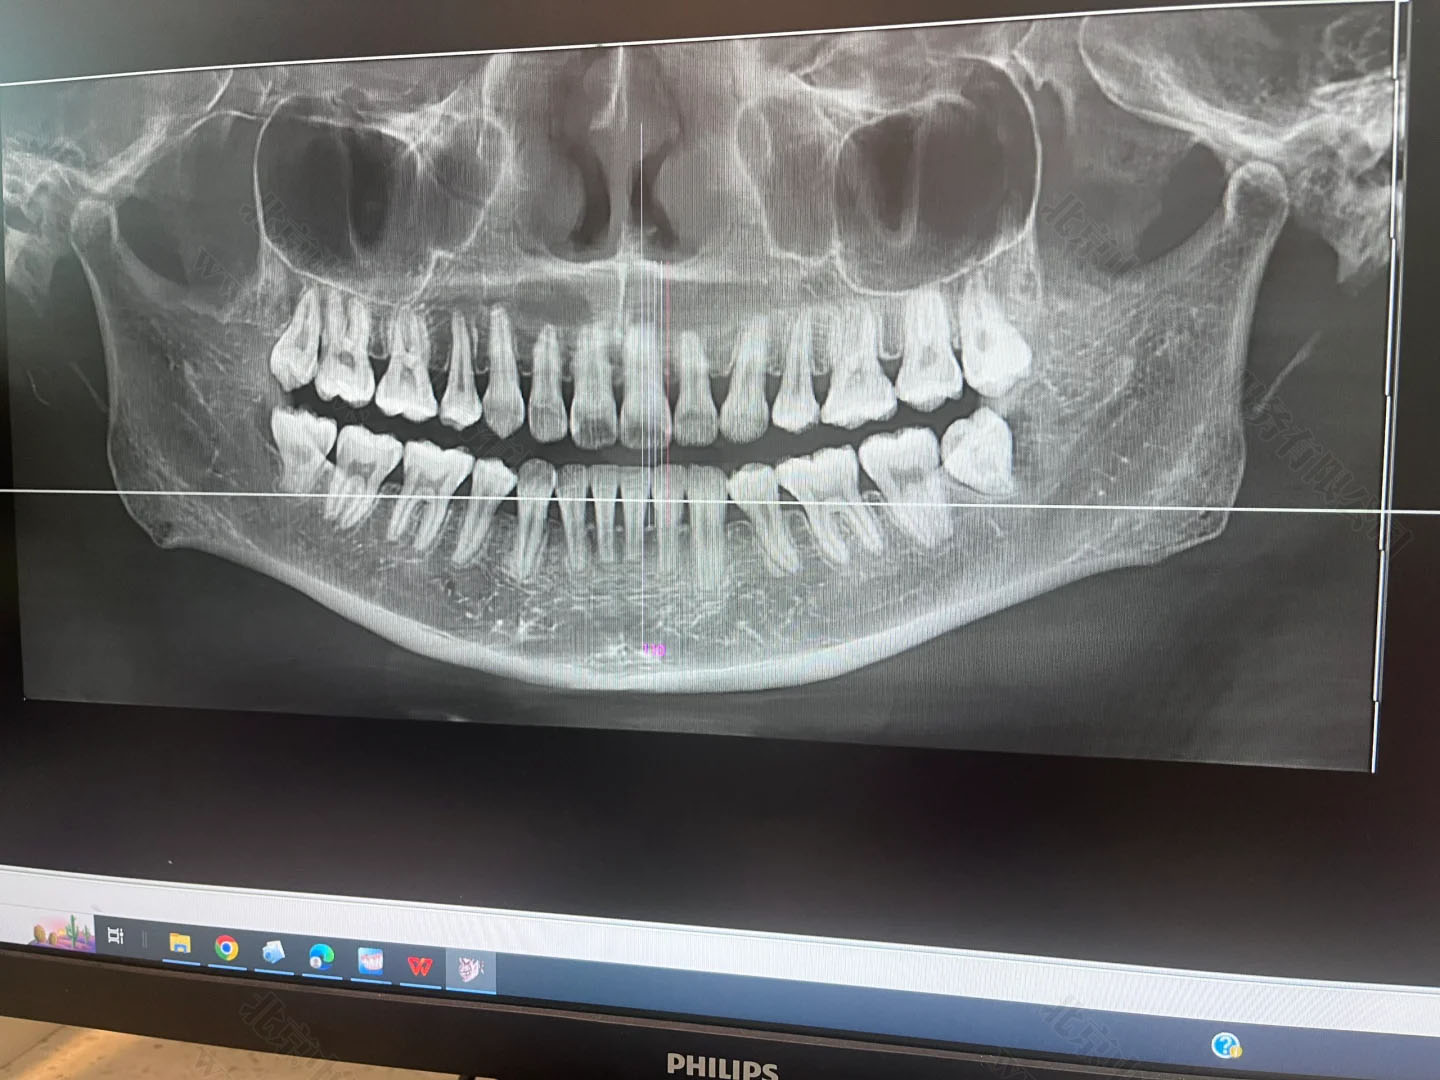

只要是裝了牙片機,不管是常規(guī)拍片還是全景片,這類設(shè)備都屬于放射類診療儀器,必須先提交項目的放射防護(hù)預(yù)評價報告,也就是確認(rèn)這個設(shè)備對人有沒有輻射危害,能不能安裝和使用。

在施工前,這個報告必須提前交到北京市衛(wèi)生部門審核。審批通過了才能動工裝修,否則一切都白忙活。牙片雖然是“輕放射”,但防護(hù)的流程跟CT、核磁一樣,不能跳過。

項目完工后也不是馬上就能拍牙片,還得請專業(yè)機構(gòu)做一個職業(yè)病危害控制效果評價,就是看你這機器在使用過程中,周邊有沒有多余輻射,會不會對醫(yī)生、患者和旁人造成傷害。做完后,還得向衛(wèi)生部門提交設(shè)備驗收申請,包括檢測報告、施工資料等一整套材料。

只有經(jīng)過這道驗收關(guān),診所才可以拿到《放射診療許可證》,正式開展拍片業(yè)務(wù)。這個流程平均要花上兩三個月,不提前準(zhǔn)備就容易耽誤診所開張。